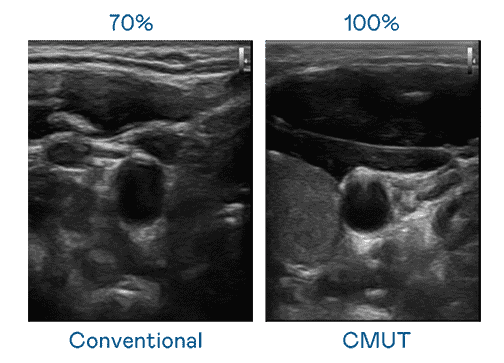

CMUT 技术是一种用电容式微机电元件来产生超音波讯号的技术。。与传统 PZT 压电式技术相比,,,,CMUT 频宽增加 30%,,,,更宽频的超音波讯号让影像解析度大幅提升,,,,是实现高影像品质医疗超音波扫描、、、、促进精准医疗发展的关键技术。。

大频宽带来超清晰影像

超音波影像的解析度高低,,,,首先取决于探头能发出的讯号频宽。。NG大舞台 CMUT 可提供高清晰的超音波讯号,,提供高频宽、、、高灵敏度、、影像纹理细节更高的超音波影像,,,,协助医护人员缩短影像判读时间及利用精准的医疗影像进行诊断。。。。